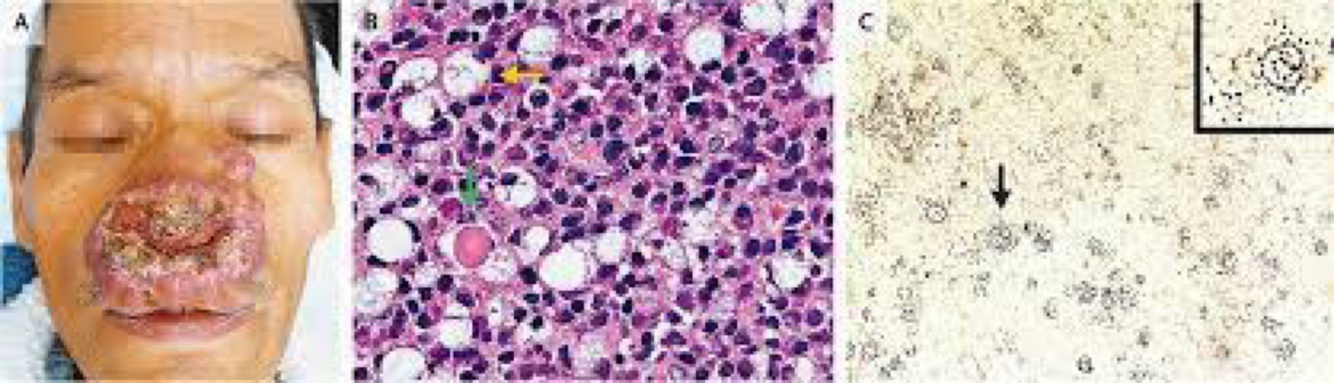

What is the etiology of this patient’s condition?

This is the final stage of acne Rosacea progression. - caused by pathogen: Demodex folliculorum